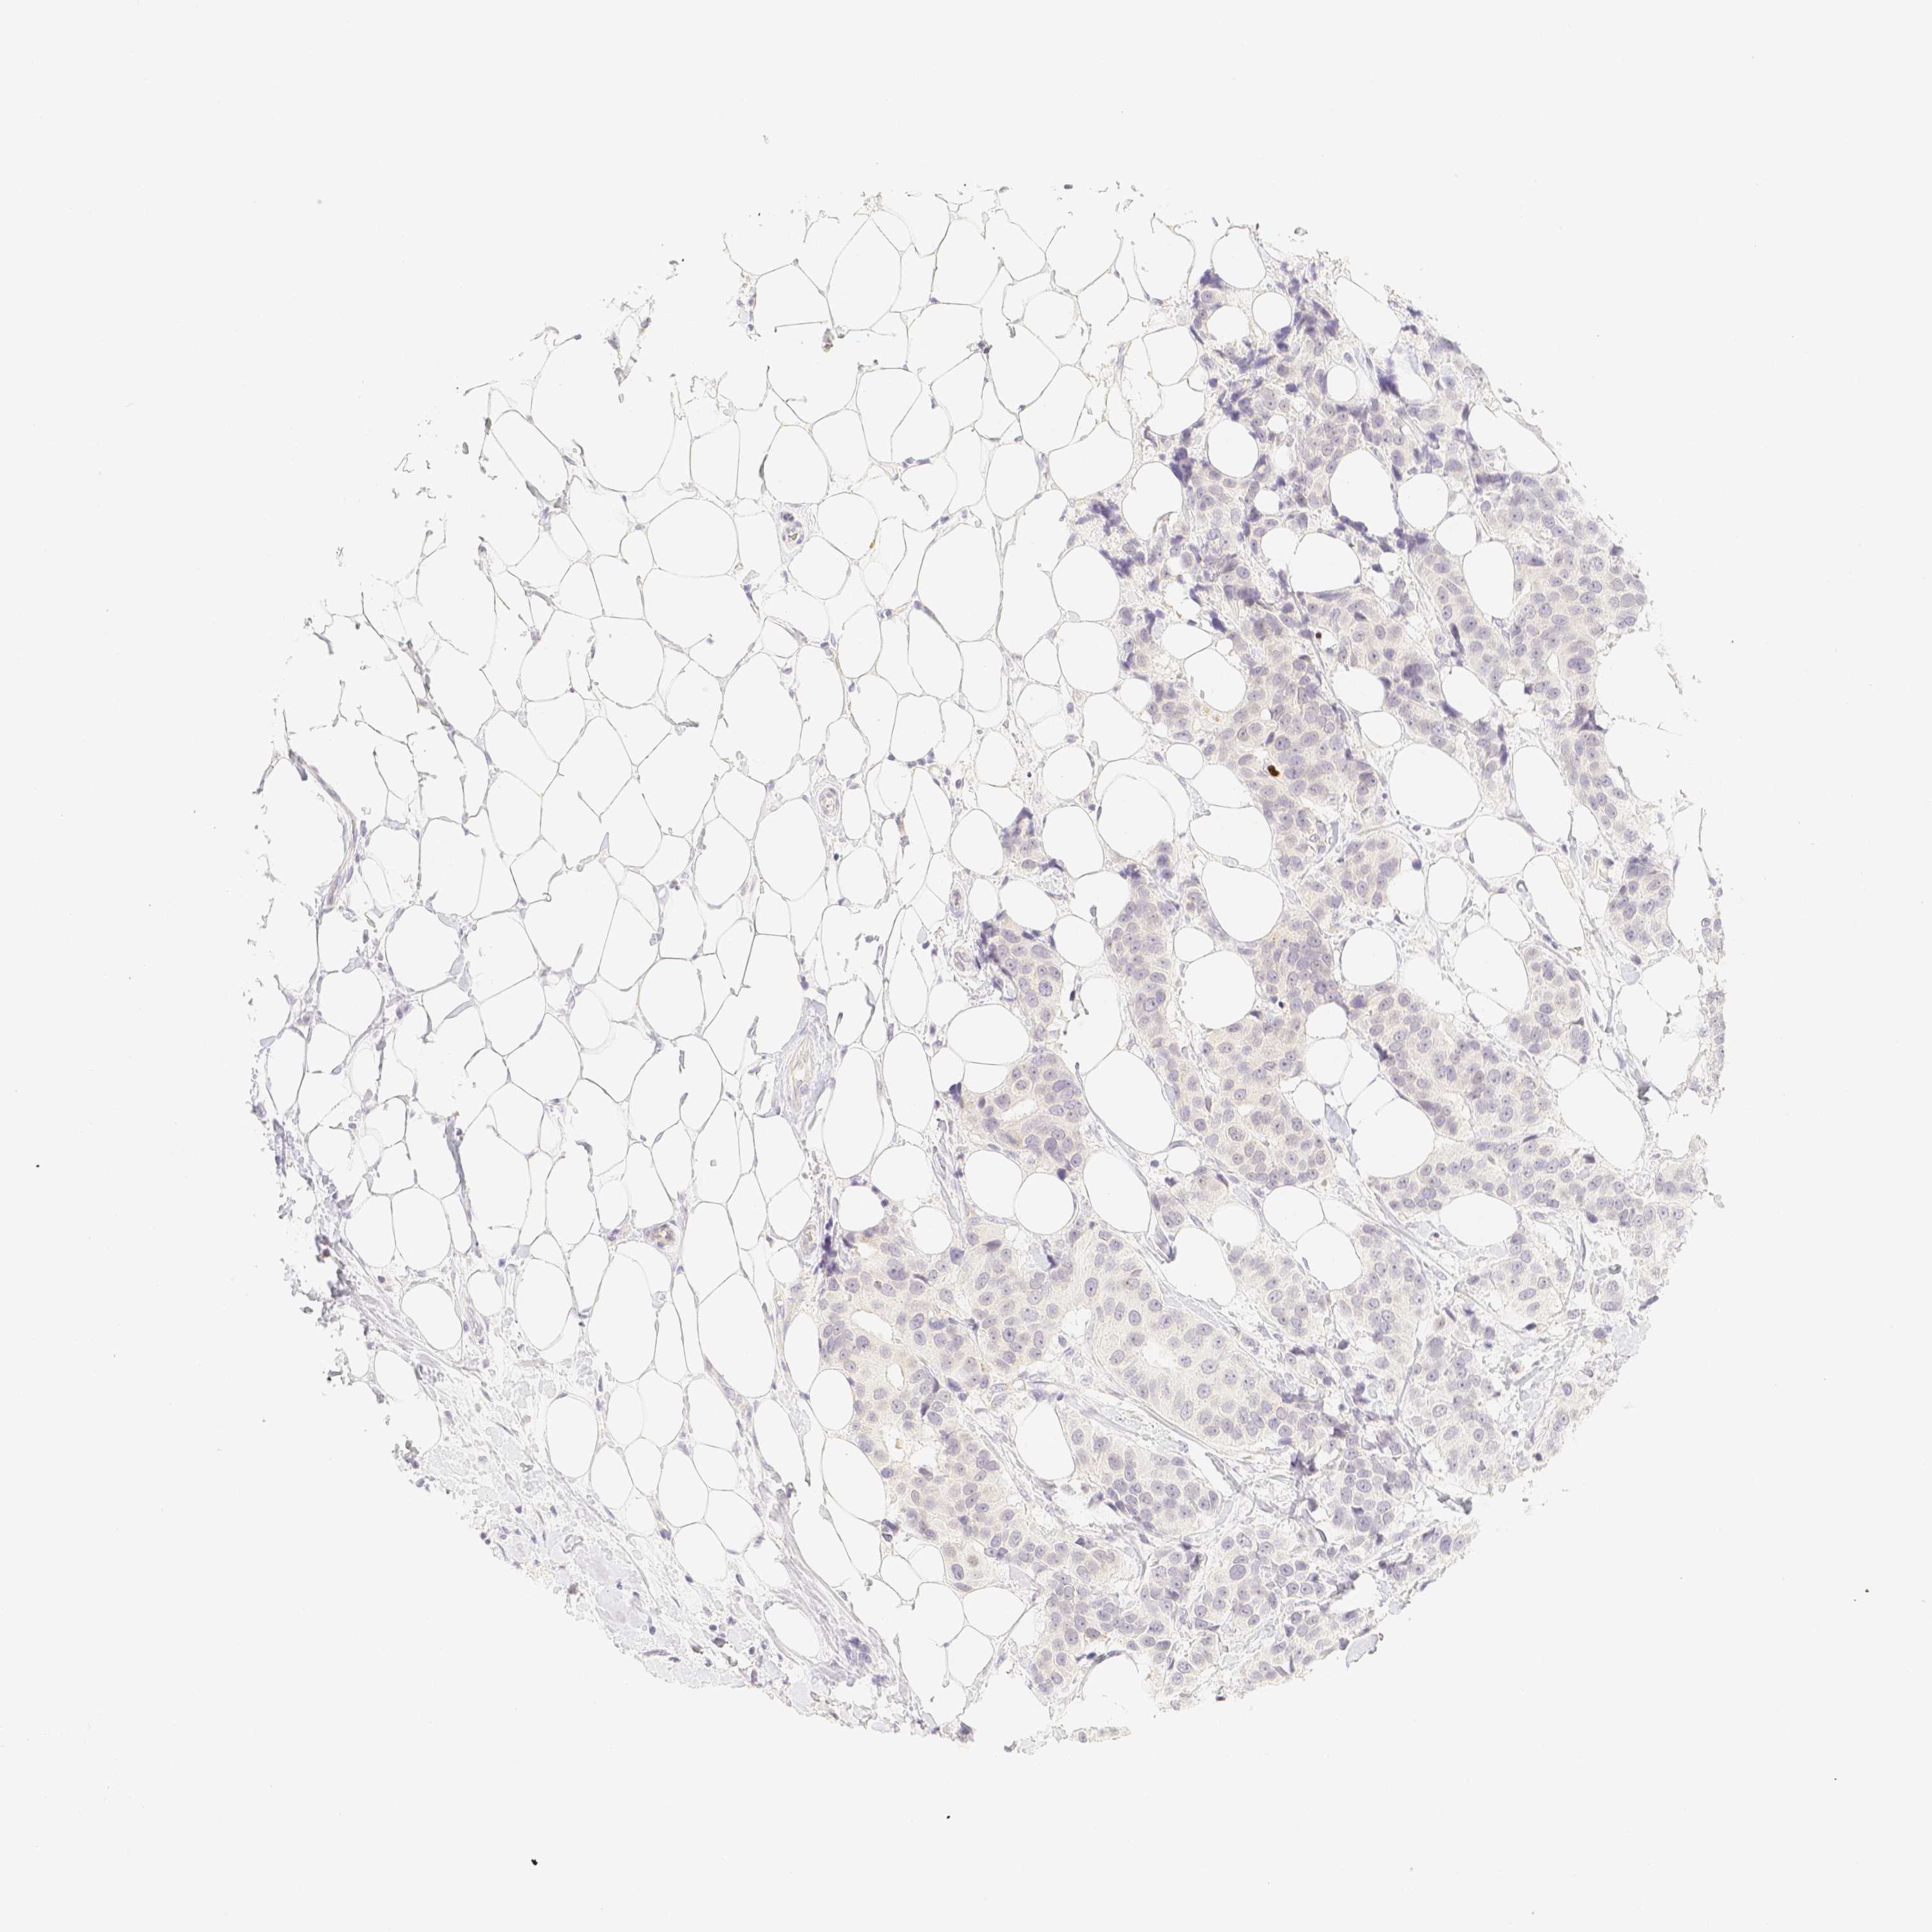

CANCER BREAST CANCER Show tissue menu

BRCA TCGA BRCA VALIDATION PROTEIN EXPRESSION

Breast cancer

Human cancer

Breast invasive carcinoma